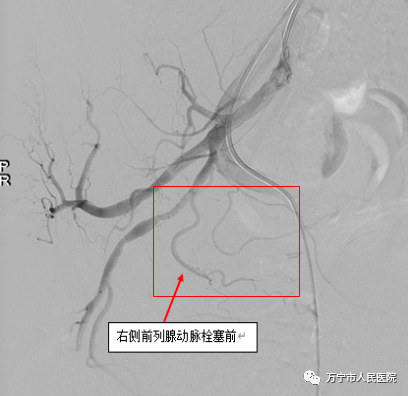

右侧髂内动脉造影显示前列腺动脉

栓塞后造影复查,前列腺动脉消失

我院介入诊疗科高西杰主任通过微导管超选择插管进入前列腺动脉并成功实施栓塞,通过对前列腺供血动脉注射栓塞剂阻断前列腺血供,从而使前列腺组织部分缺血坏死,最终使得膀胱以下梗阻解除和症状缓解。术后5天患者临床症状明显改善,遗尿消失,小便通畅且次数减少,无并发症,顺利康复出院。